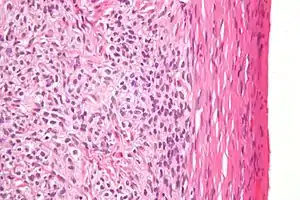

| High magnification micrograph of a thecoma. H&E stain. | |

Low magnification micrograph of a thecoma showing compression of the ovarian cortex (right of image). H&E stain.

Microscopically, the tumour cells have abundant lipid-filled cytoplasm.